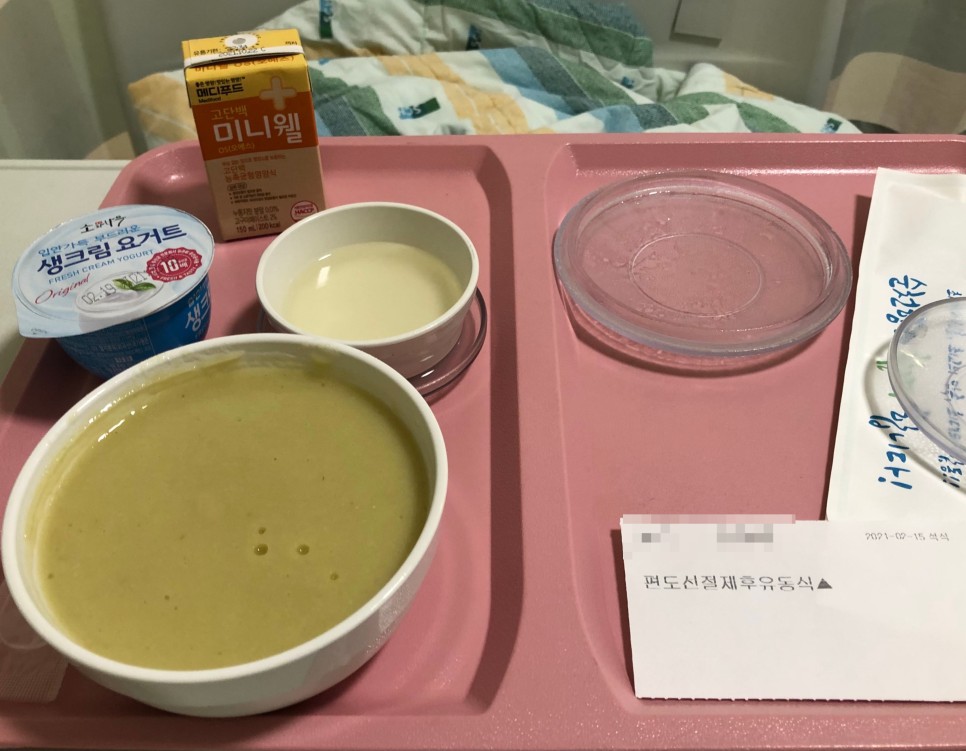

수술 당일 저녁

수술 당일 저녁이에요.저는 죽은 거의 못먹고 요구르트만 먹었어요…요구르트는 정말 맛있었어요.

밥을 먹고 있는데 드디어 의사가 왔어요!제 목을 보고 많이 부었다고… 수술하면 기구가 목젖에 맞아서 부은대요

하지만 숨을 쉴수 없을정도로 부은건 아니고 그냥 참을수 밖에 없대요ㅠㅠ 일주일정도 지나면 좋아진다고 했어요!(오늘이 6일째인데 목젖이 확 작아졌어요!)

너무 배불러서 먹은 것도 없고 액셀란트 2개 먹었어요 이것도 좋아요!

약 다 먹으면 가루약+시럽약 먹어요!